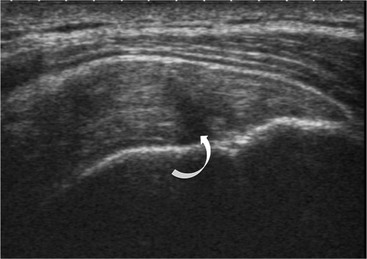

The primary sign of a rotator cuff FTT is a focal deficiency of the tendon (Figs. 46-4 and 46-5). This nearly always occurs at the tendon insertion on the tuberosity. The margins of the tear are best delineated when there is fluid within the tendon defect. Secondary signs of an FTT include the presence of fluid in both the GHJ and SAB, and flattening or concavity of the subacromial fat plane.

PTTs are less reliably demonstrated by both MRI and US, and it may be difficult to differentiate tendinopathy from partial tears. Focal clefts, tears, or tendon thinning affecting the articular margin of the footprint of the tuberosity are most common (Figs. 46-6 and 46-7). Tendon thickening is not always present. It is important not to mistake magic angle phenomenon on short TE MR sequences or anisotropy on US as evidence of tendinopathy.2